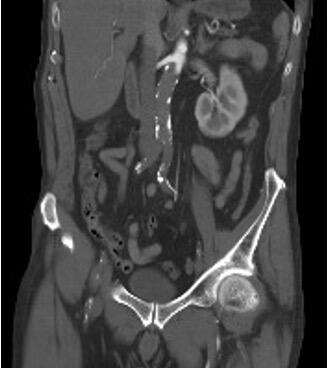

He presented to the ED 5 days later with pain, paralysis, and bilateral anesthesia of the lower limbs of 3 hours' duration, presenting with pulselessness at any level, with cutaneous lividity in the abdomen and both thighs on physical examination. The electrocardiogram showed new-onset AF, and an aorta computed tomography (CT) scan revealed complete acute occlusion of the infrarenal aorta and bilateral iliac arteries, along with chronic occlusion of the LEIA (Figure 1).

The patient was transferred to the hospital ward and discharged on the 8th postoperative day with closed fasciotomies and preserved bilateral pedal pulses. During the hospitalization, a follow-up CT scan for his bilateral pneumonia showed a patent endograft without leaks (Figure 2). Two months later, the patient received treatment for his vocal cord carcinoma from the otolaryngology department through radiotherapy. In the most recent outpatient follow-up 1 year ago, he maintained distal pulses, and ultrasound evaluation showed the endograft without leaks and patent femorofemoral bypass.